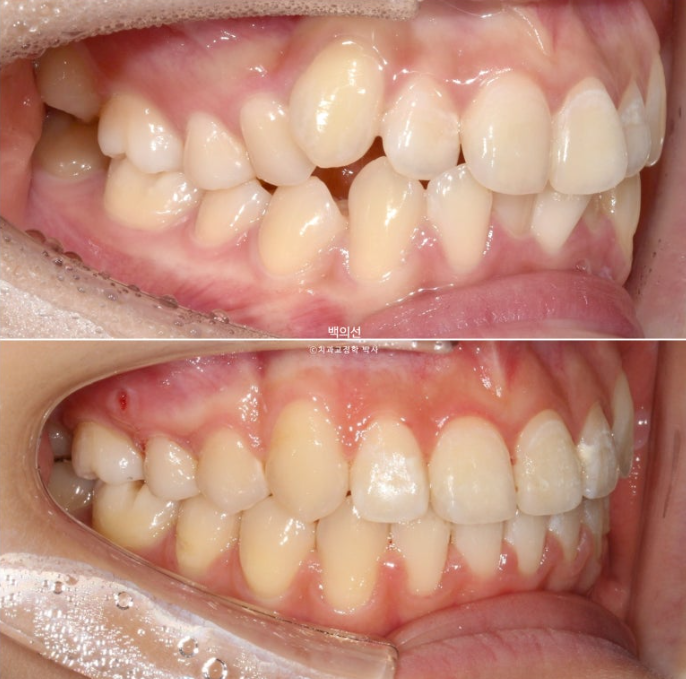

25.07

교합은 좌우 정 1급을 달성했으며 좋습니다.

23.05~25.07

2년 2개월간 치근흡수는 없으며 치근평행도는 좋습니다.

특히 송곳니 덧니 쪽으로 쓰러져 있던 송곳니와 작은어금니 뿌리 치축 개선이 눈에 띕니다.

환자분이 인비절라인 장치를 잘 껴주었다면 굳이 클리피씨 붙이지 않고서도 치료결과가 좋았을텐데 하는 아쉬움이 남지만, 환자분 개개인이 처한 상황이 모두 같을 순 없습니다.

약간 돌아갔지만 결과가 좋아 다행입니다.